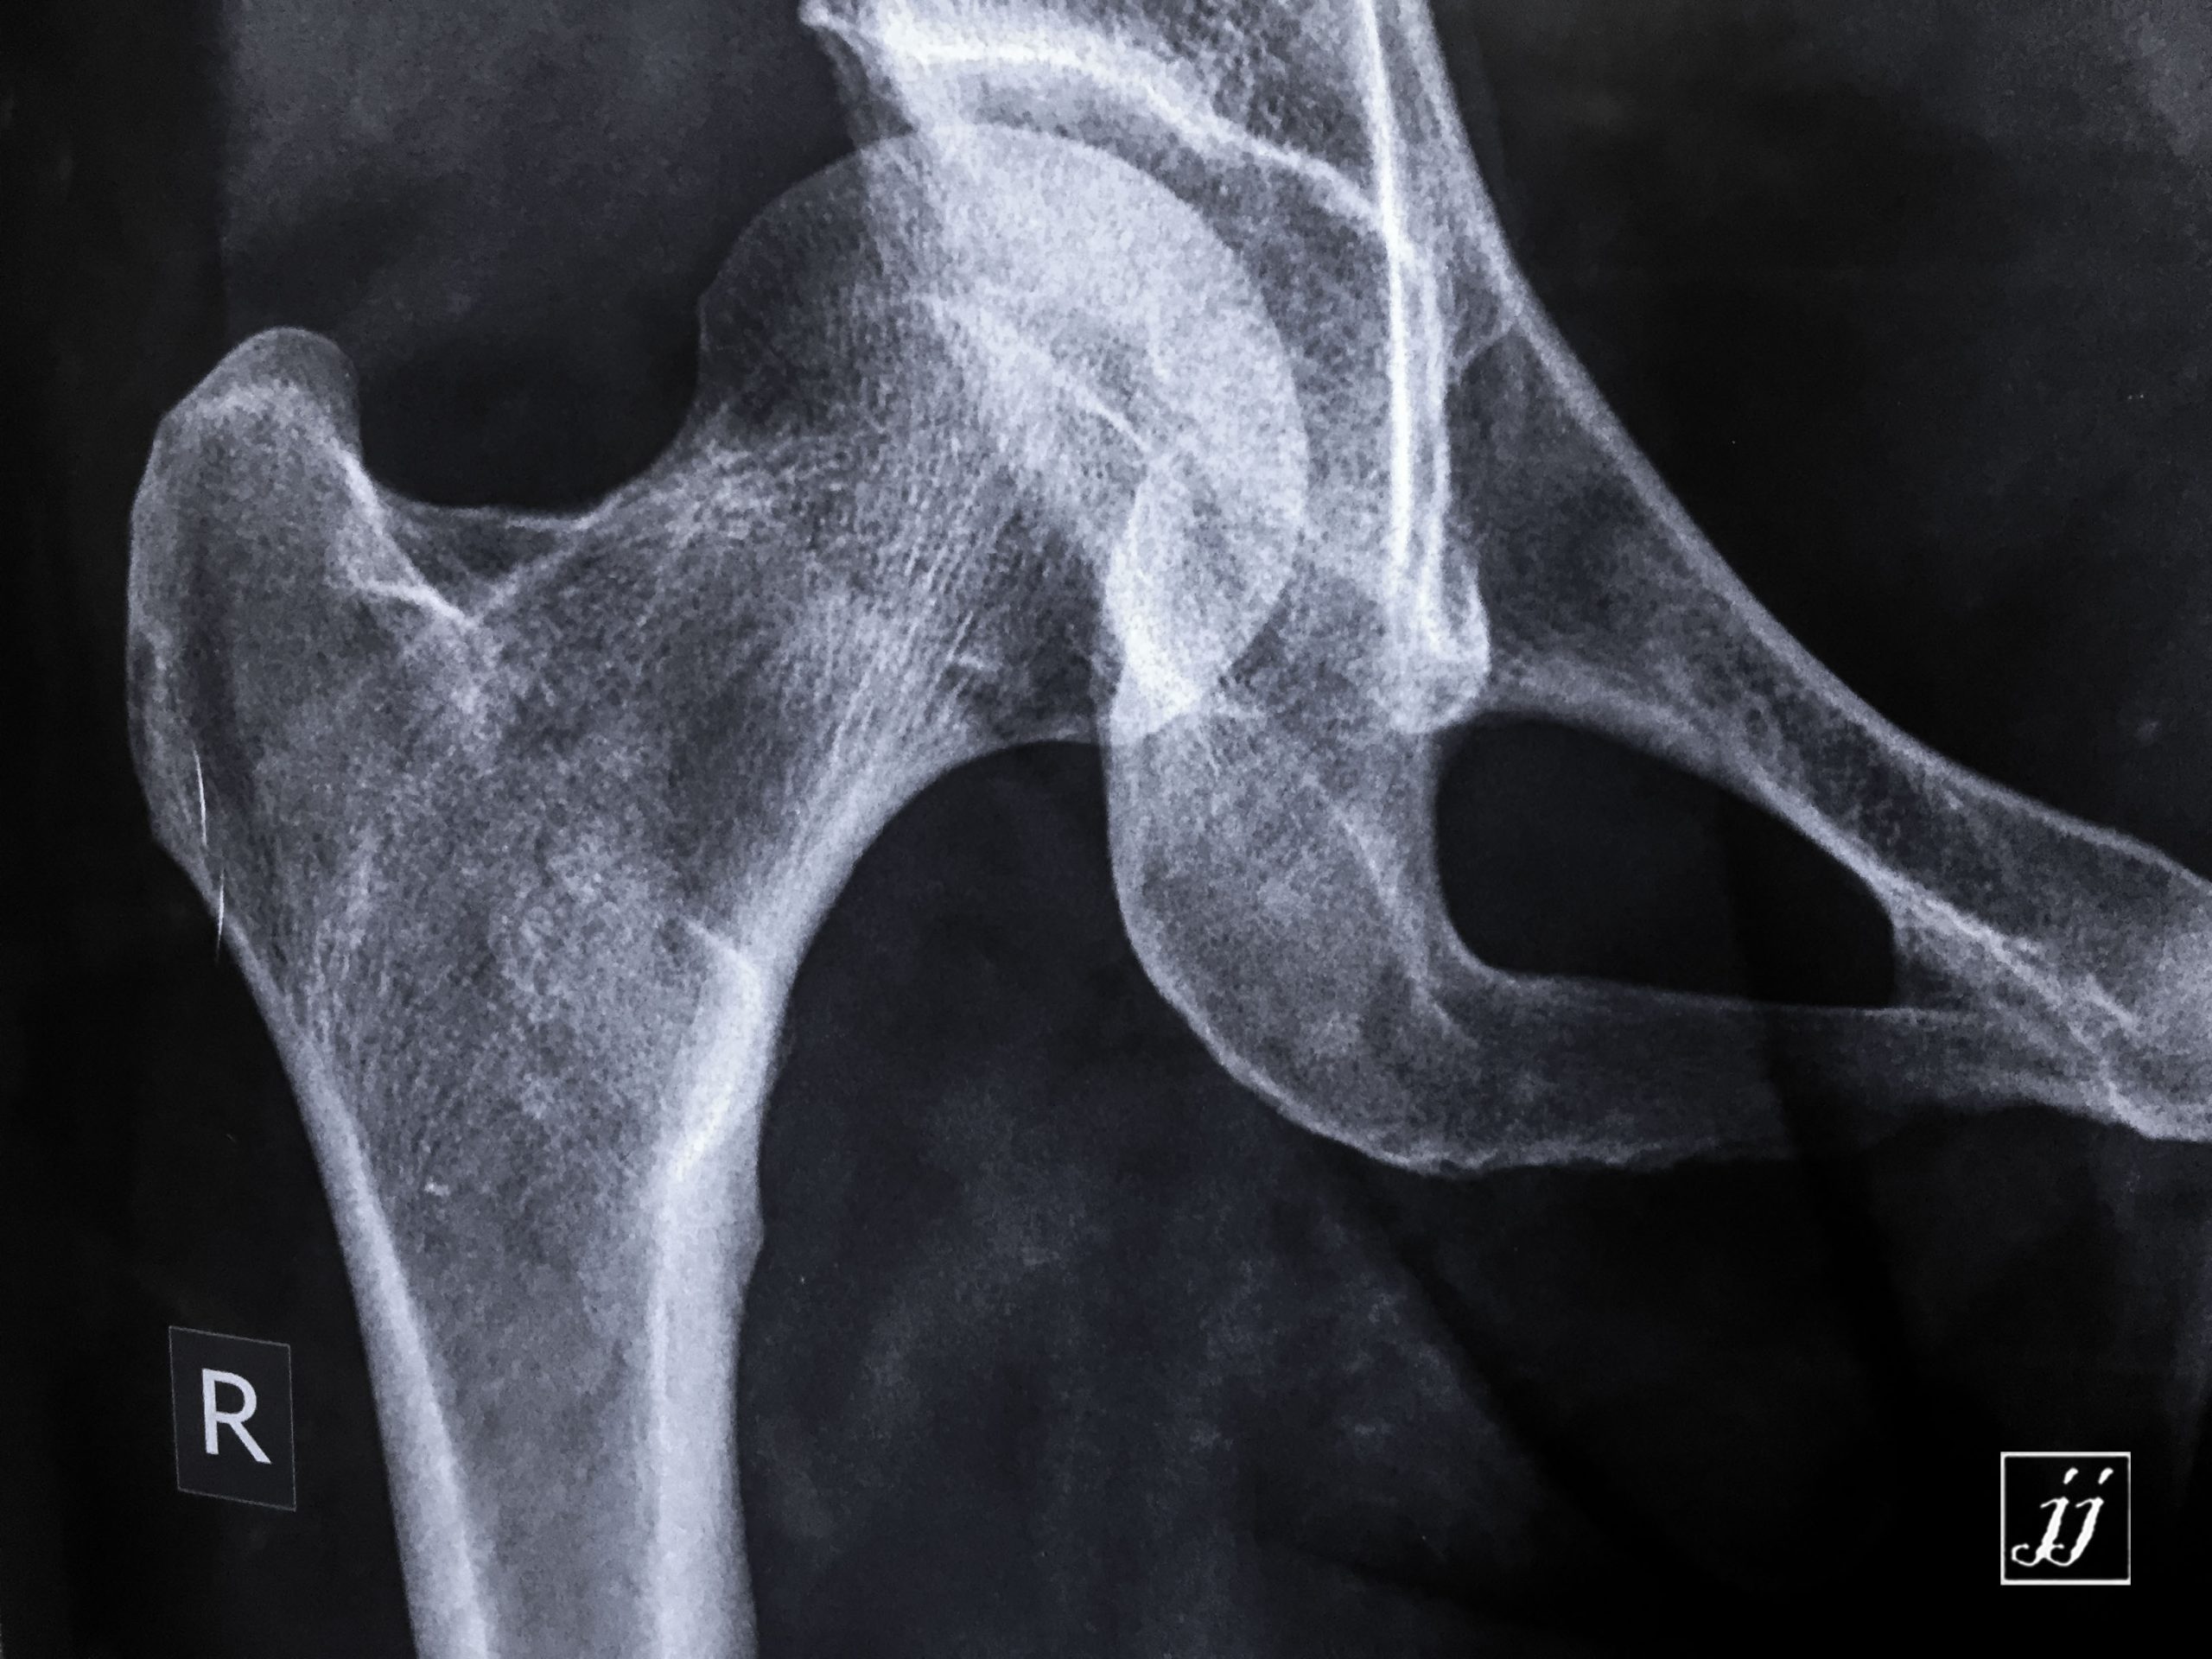

MSK- detached fracture of lesser trough chanter (3)